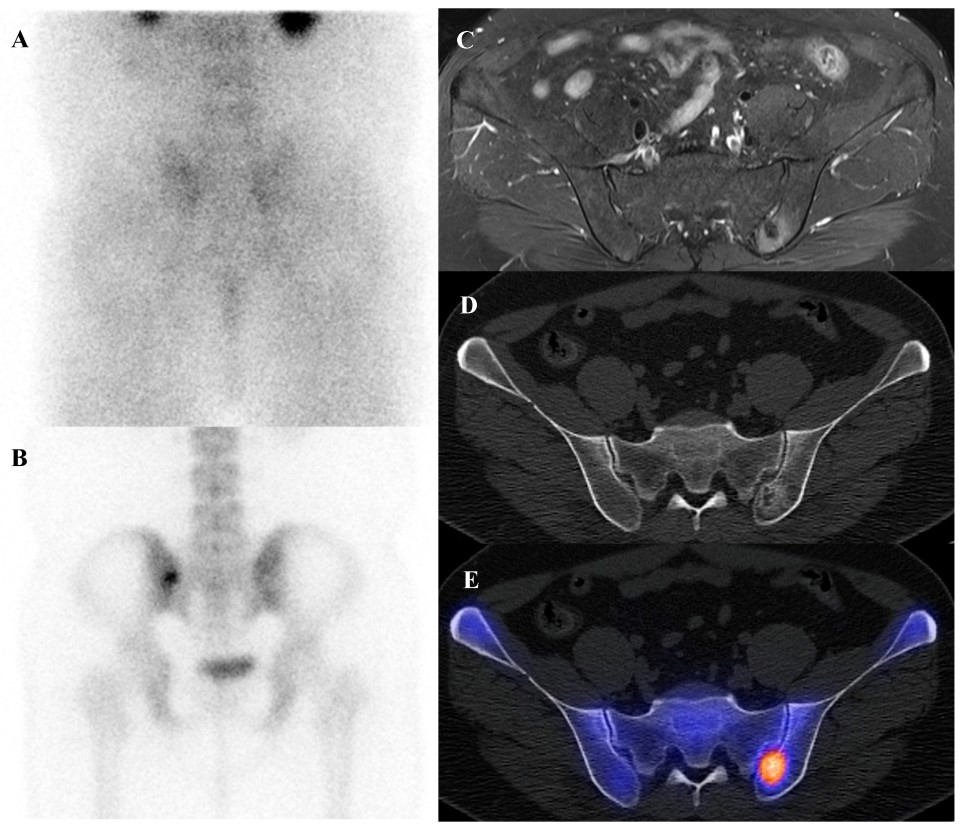

Osteoid osteoma is a small, benign bone-forming tumor that classically presents in young males with nocturnal pain relieved by nonsteroidal anti-inflammatory drugs. It has a pathognomonic appearance on a three-phase bone scan. Due to its highly vascular nidus and intense osteoblastic activity, the lesion demonstrates increased perfusion on flow images, hyperemia on blood pool images, and intense, focal uptake on delayed images [59]. This intense focal uptake on the delayed phase is often referred to as the “double-density sign,” characterized by a central hot spot of extreme avidity (the nidus) surrounded by a less intense but still avid zone of reactive sclerosis [60]. Bone scintigraphy has a sensitivity approaching 100% for detecting osteoid osteomas [61]. Although benign lesions may also demonstrate increased tracer uptake, reducing the specificity of this technique, the integration of SPECT/CT substantially enhances diagnostic accuracy by providing precise anatomic localization and improved lesion characterization [62]. It is particularly valuable for localizing small or intra-articular lesions that may be occult or difficult to identify on plain radiographs. While [18F]FDG PET/CT usually shows high metabolic activity in the nidus [63], some osteoid osteomas demonstrate no uptake [64]. Despite this variability, [18F]FDG PET/CT can be useful for assessing treatment response [65]. Figure 4 shows an osteoid osteoma of the femoral neck, where bone scintigraphy and SPECT/CT clearly identified the nidus with intense uptake in concordance with MRI findings.

Figure 4.

An 11-year-old male with osteoid osteoma of the left femoral neck. (A) T2-weighted fat-suppressed magnetic resonance imaging shows a lesion with high signal intensity and a sclerotic rim in the medial cortex, accompanied by perilesional edema (“half-moon sign”). (B,C) Bone scintigraphy demonstrates increased uptake in the left femoral neck on both blood pool and delayed phases. (D–G) Bone single-photon emission tomography/computed tomography reveals an osteolytic lesion with a central nidus and intense uptake.